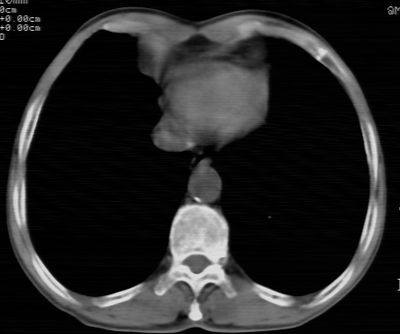

标题: CT24783:m71,既往肺心病史3年,现咳嗽,憋喘。 [打印本页]

标题: CT24783:m71,既往肺心病史3年,现咳嗽,憋喘。

1、左肺上叶spn,毛刺+分叶+血管集束征,考虑周围型肺癌可能性大

2、全小叶性肺气肿。

1)左肺上叶周围型肺癌可能。2)两肺全小叶型肺气肿。